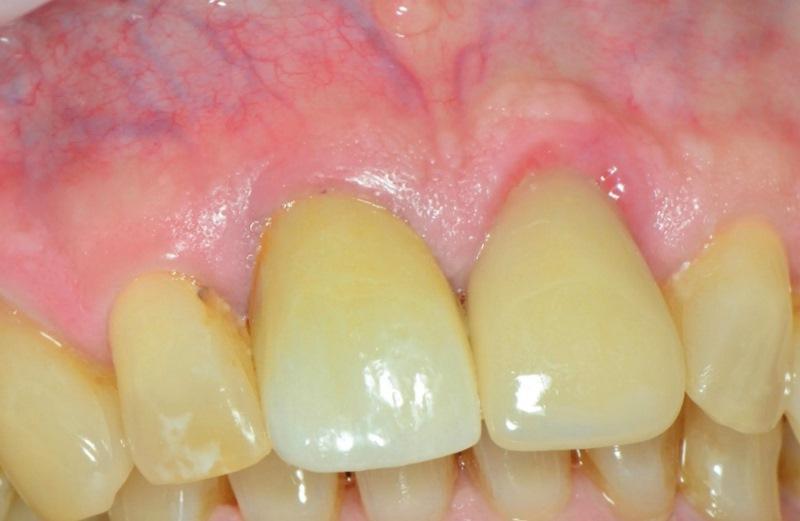

Пациент, мужчина 78 лет, обратился на консультацию по поводу перелома правого верхнего центрального резца (зуб 1.1) (Фото 1). Он пользовался временным частичным протезом для замещения коронки зуба. Пациент выразил желание заменить зуб имплантатом. При изучении анамнеза значимых соматических заболеваний не выявлено.

Фото 1. Пациент обратился с переломом правого верхнего центрального резца (зуб 1.1) на уровне десны.